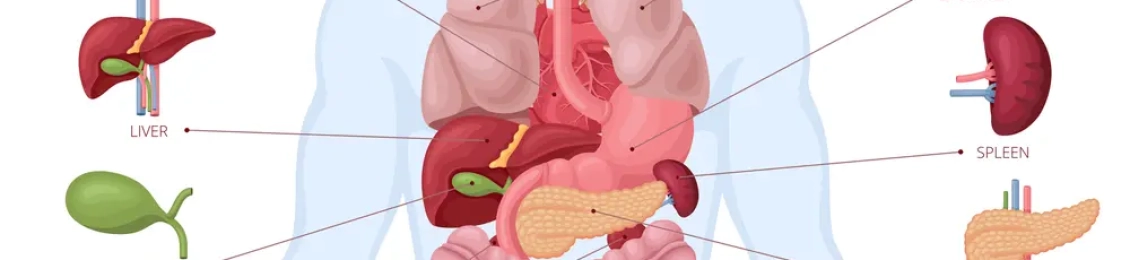

دائمًا ما يريد الإنسان سلامة اعضاء الجسم الداخليه لديه، ولهذا أوصى الأطباء بضرورة عمل كشف طبي كلي دوري على جميع أجهزته مرة على الأقل كل عام للاطمئنان على صحته وسلامته ولسرعة اكتشاف المرض في مرحلته الأولى، كما يجب مراجعة أطباء الأشعة بمجمع الطب المتميز بالمدينة المنورة الذي يوفر جو خاص ومريح من الخدمات المتوفرة بالأشعة […]